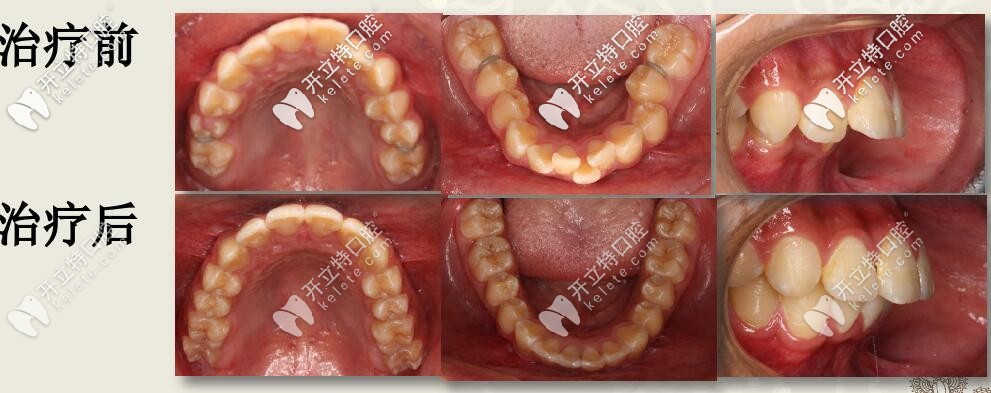

肉眼可見(jiàn)上前牙唇傾,輕度擁擠 下頜牙弓寬度窄,前牙區(qū)擁擠,后牙去舌傾明顯,前牙深覆蓋,深覆合

結(jié)束后,牙列整齊,深復(fù)蓋明顯改善。